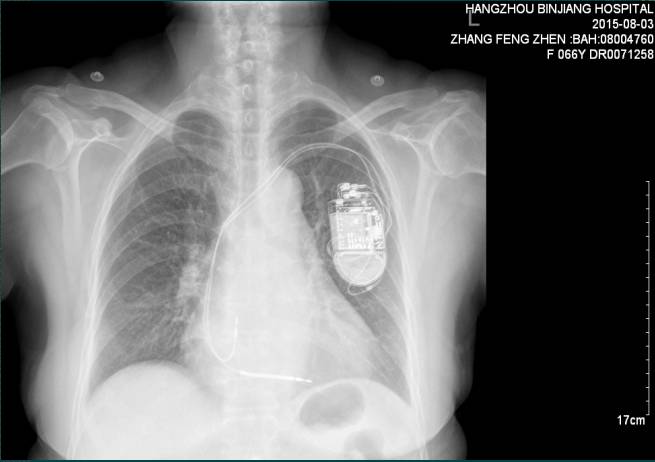

1.女性,66岁,杭州本地居民.于2015.08.03入院。

2.反复晕厥7年,ICD植入后5月,再发晕厥后5天。

3.患者7年来反复出现晕厥,5月前症状再发,每次持续时间数十秒至数分钟,结合心电图、心超、冠脉造影结果,诊断“扩张性心肌病”心电图提示非持续性室速,接受双腔ICD植入术;5天前,患者类似晕厥症状再发,发作前驱有心悸和胸部不适感,无发热,无头痛,无四肢抽搐;

②冠脉造影:

冠脉造影未见明显异常;

⑥冠脉造影(2015.03.02)